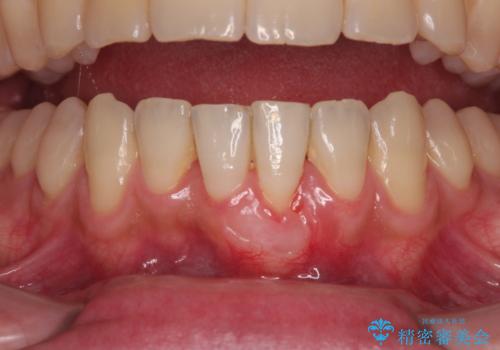

一度の処置で十分に根面被覆ができました。

舌側に歯石が溜まりやすく、やや出血が認められるため、定期的なクリーニングが大切となってきます。